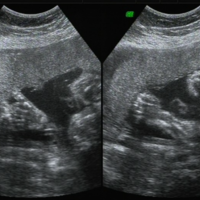

孕中期三维彩超照出来丑是因为胎儿发育还没有完全。三维彩超是一种高级的超声检查方法,可以提供更加清晰、立体感强的胎儿图像。在孕中期进行三维彩超可以更清楚地观察胎儿的面部、四肢、器官等结构,有助于了解胎儿的发育情况和进行初步的筛查。胎儿的发育情况也可能影响到图像的外观。有时候,因为胎儿的生长状况而导致一些部位看起来不太完美或不够美观。有时候,孕中期三维彩超照出来的图像可能看起来不太美观,可能会让人感觉

孕中期三维彩超照出来丑是因为胎儿发育还没有完全。三维彩超是一种高级的超声检查方法,可以提供更加清晰、立体感强的胎儿图像。在孕中期进行三维彩超可以更清楚地观察胎儿的面部、四肢、器官等结构,有助于了解胎儿的发育情况和进行初步的筛查。胎儿的发育情况也可能影响到图像的外观。有时候,因为胎儿的生长状况而导致一些部位看起来不太完美或不够美观。有时候,孕中期三维彩超照出来的图像可能看起来不太美观,可能会让人感觉

孕中期只做三维来排畸不做四维彩超可以。三维彩超和四维彩超都是属于彩超的一种,两者都是排除胎儿畸形的超声检查,一般只要做其中一个就可以。三维超声可以提供更为清晰的胎儿图像,有助于检测胎儿的器官结构和发育情况,而四维彩色多普勒超声则可以提供动态的胎儿图像,更直观地显示胎儿的活动和表情。具体选择哪一个可以听取医生的建议。在孕期进行排畸检查通常会选择进行彩色多普勒超声检查,包括三维和四维彩色多普勒超声。三

孕五六个月做二维彩超检查最好。二维彩超就是一种清晰度比较高的黑白b超,以及彩色多普勒技术的共同检查手段。它具有b超的所有特点以及功能。它不仅能够拍摄到在不同孕周时胎儿的发育情况,还可以发现胎儿是否有异常现象。通常建议在怀孕大约是20周左右进行二维彩超检查,这个时候通常可以检查胎儿的器官发育情况、男女、胎盘位置等重要信息。二维彩超相对的检查项目比较简单,一般在孕五六个月的时候会做二维彩超,其实除了二

孕期做完彩超之后从结果单子看男女是网上流传比较广的一个说法,但实际上这种说法的准确度是不确定的。彩超是超声诊断的一种,是通过立体动态的形式呈现胎儿在子宫内的发育情况,在这个阶段胎儿的生殖特征已经显现,所以可以通过三维彩超能判断胎儿的男女。一般是通过字母、胎儿数据、孕囊大小等诀窍来进行看男看女。彩超单子3秒钟看男女的诀窍彩超是能够看出胎儿男女,但法律规定医生不得进行男女鉴定,所以就有很多人从生男宝生女宝

在生育孩子的过程中,许多父母都很期待知道自己孩子的男女,而现代科技的发展使得预测胎儿男女已经成为可能。三维彩超是超声诊断的一种,是通过立体动态的形式呈现胎儿在子宫内的发育情况。通过超声波检查的三维报告单,我们可以看到胎儿的各个方面的特征,具体怎么看有一定的诀窍,其中有些特征是可以用来识别男孩女孩的,下面来一起具体了解一下吧。三维彩超看胎儿男女诀窍孕妇做三维彩超一般是在22周-26周之间,且三维彩超